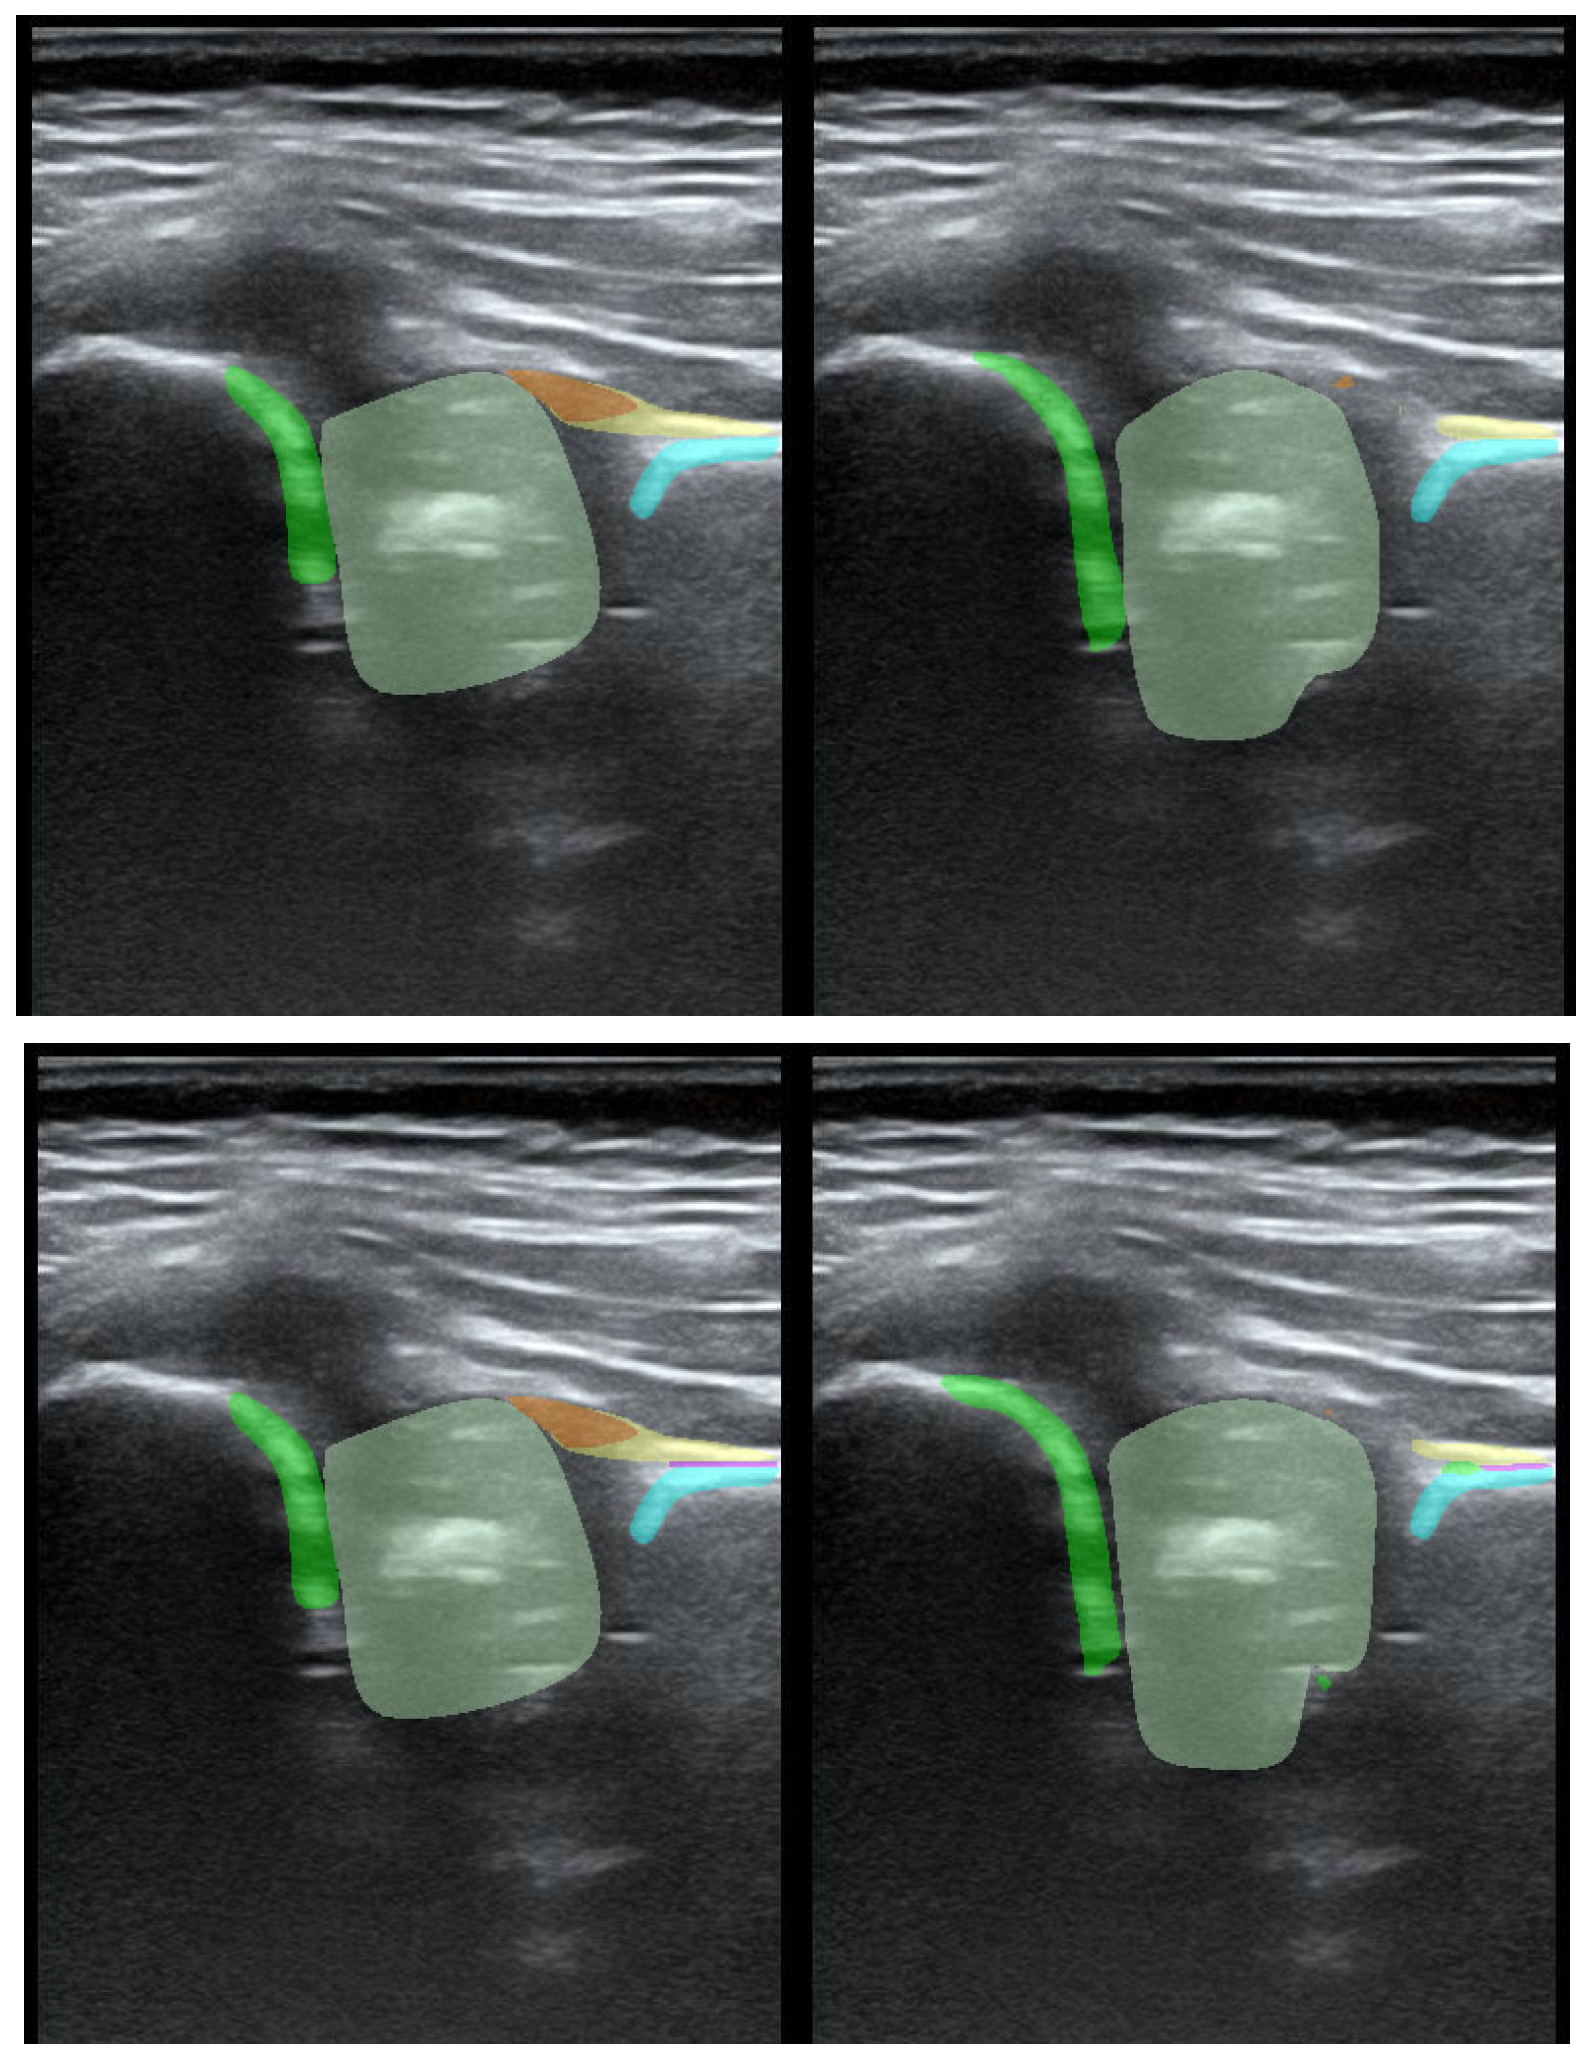

To illustrate the performance of the segmentation model, a comparison is presented between the labels obtained by the segmentation model and the ground truth labels. Two models were analyzed: Model-8 (generating segments for eight classes) and Model-5 (generating segments for five classes). Both the cases with the highest quality model labels and the cases where the model labels were less accurate are presented. Figure 3 shows one of the best cases, in which Model-5 and Model-8 accurately labeled the classes relative to the doctor’s labels. The worst-case scenario was also analyzed, in which the prediction results differ significantly from the ground truth labels (Figure 4).

Figure 3. High-quality model labels (upper—Model-8) and (lower—Model-5). Annotated mask on the left, model mask on the right.